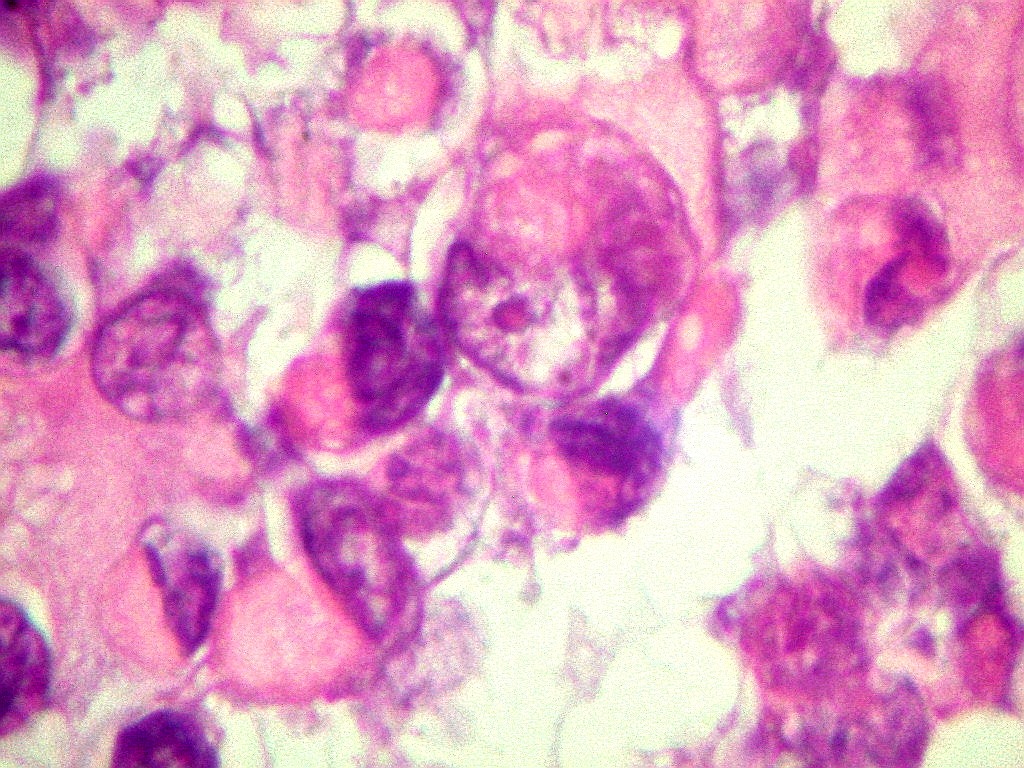

| MAP2.

Positivo citoplasmático em todas células tumorais,

indica diferenciação neuronal |

S-100.

Marcador de células derivadas da crista neural, como células

de Schwann e melanócitos, positivo em parte das células

tumorais (marcação nuclear e citoplasmática). |